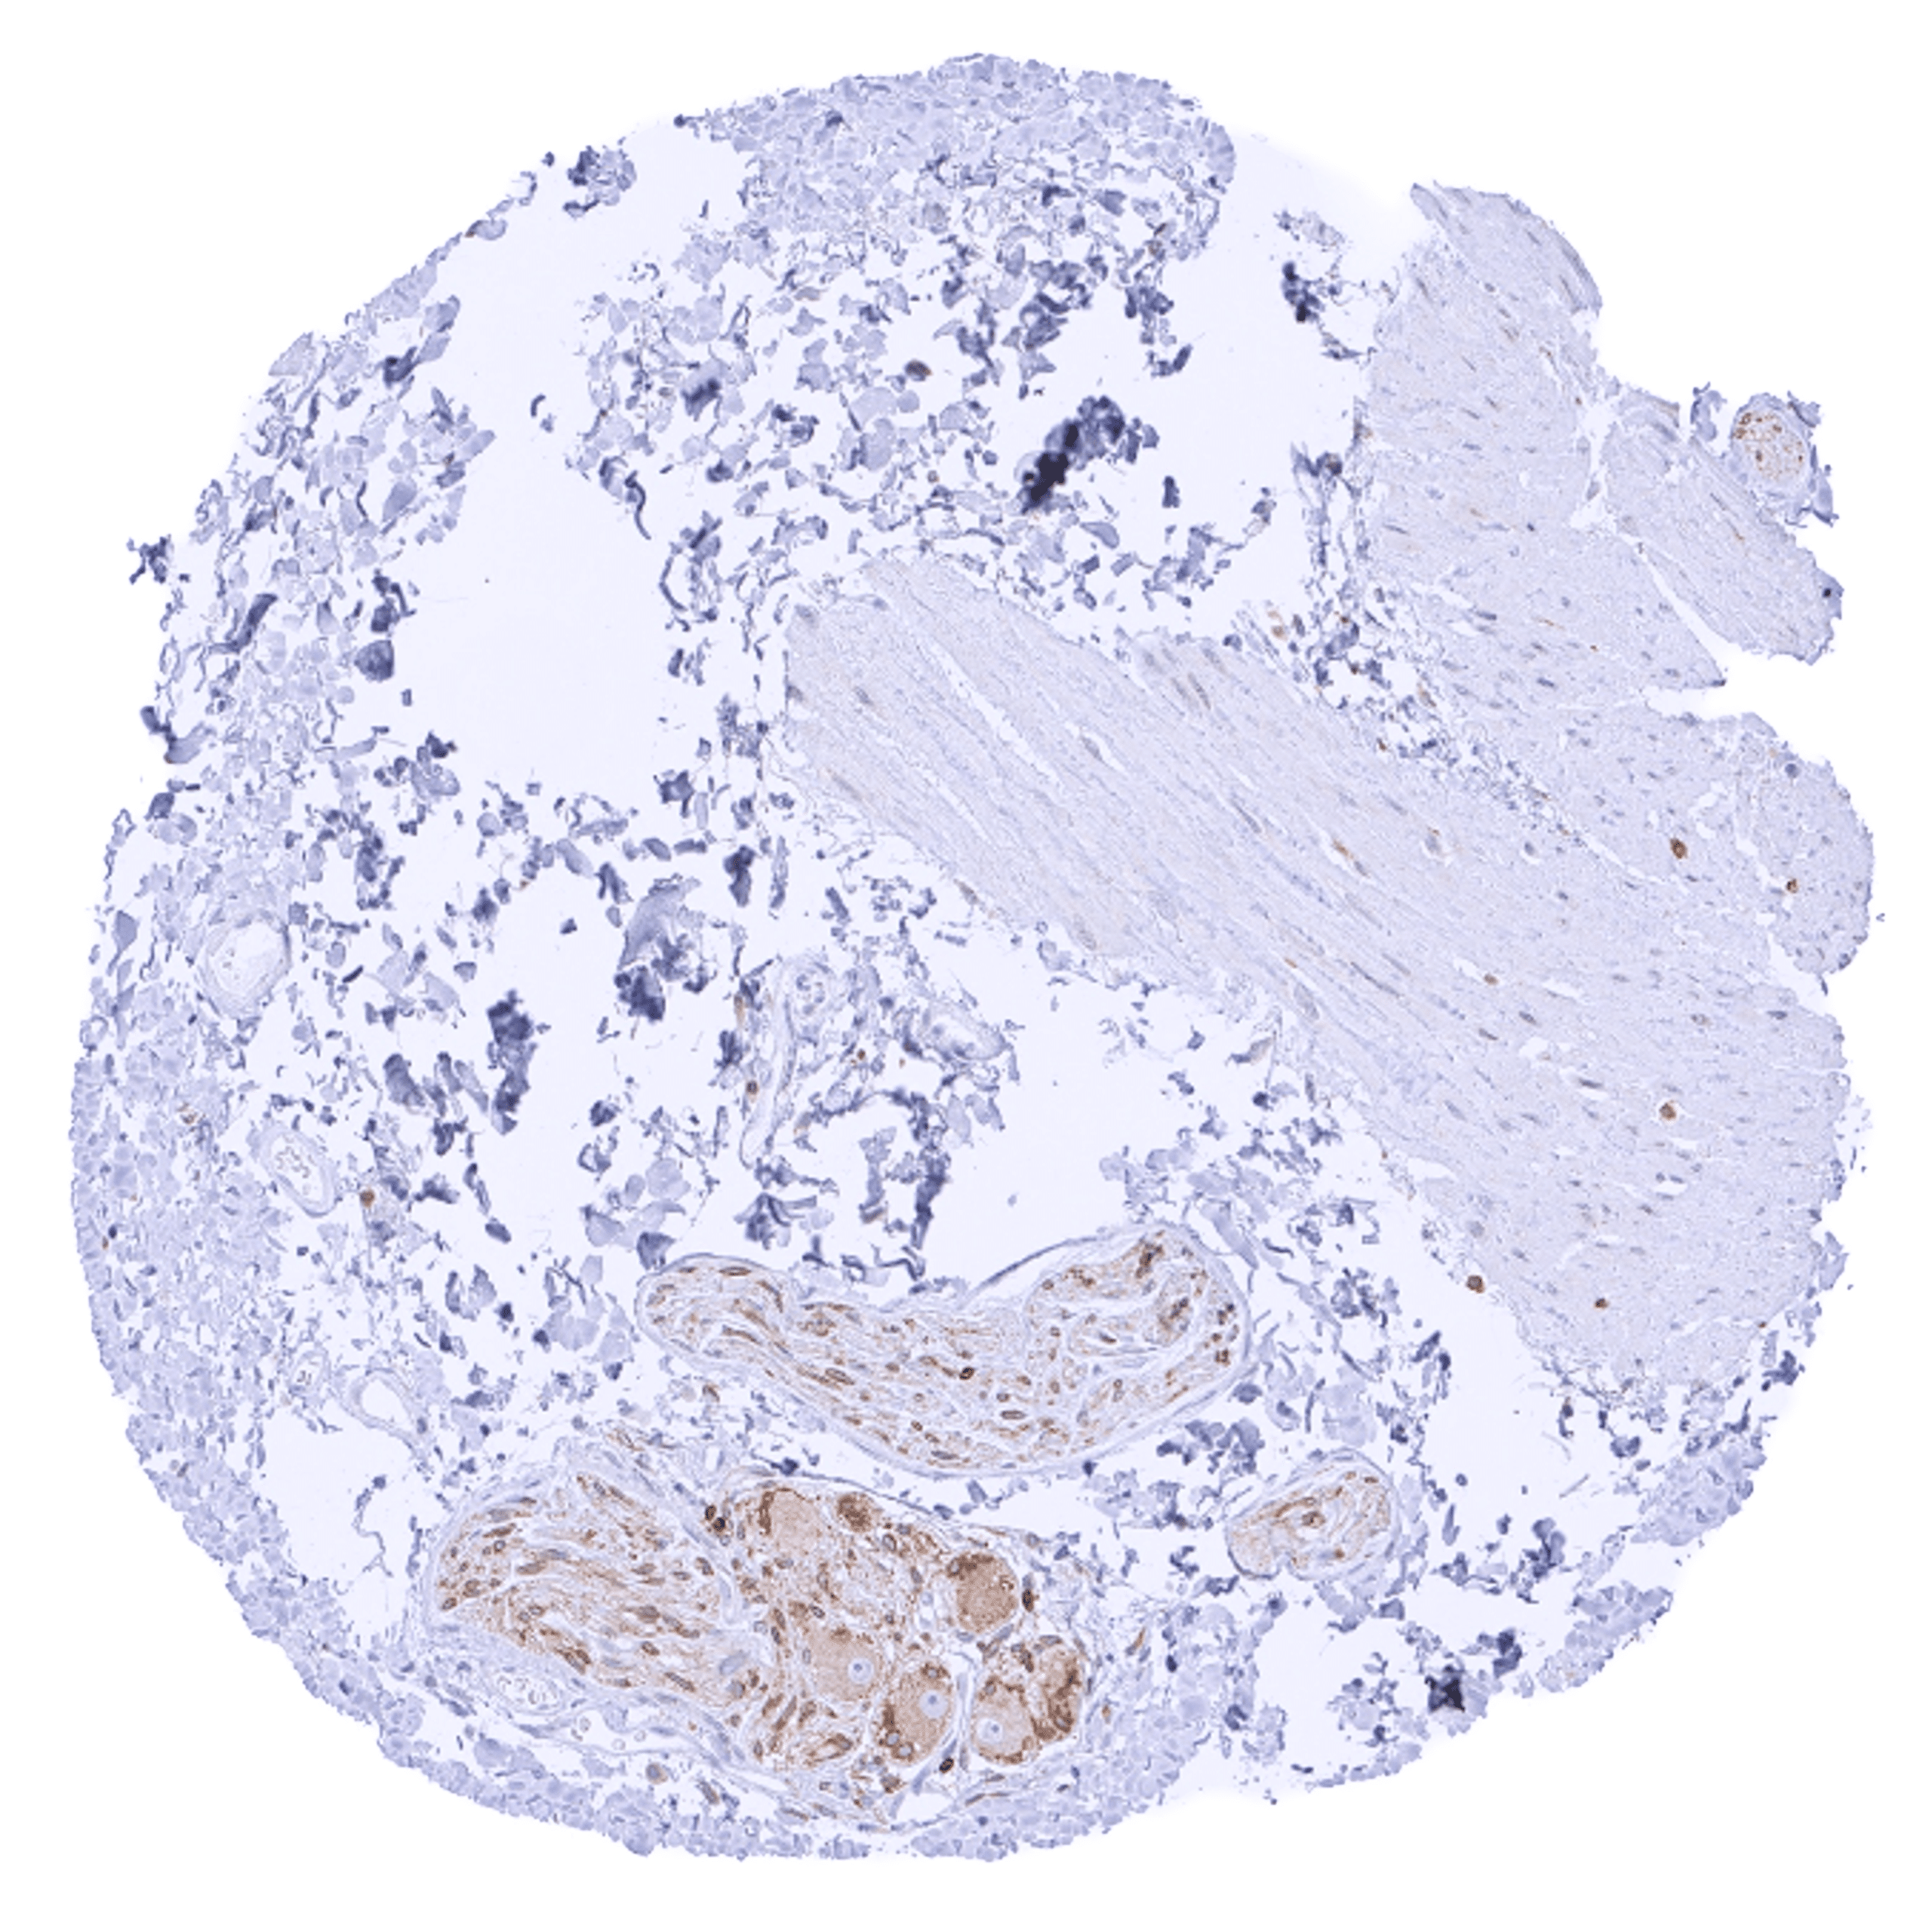

Bcl-2 expression of variable intensity can occur in all types of cancer. It is particularly common in follicular lymphoma.

Comparison of antibodies: True expression of bcl-2 in all cell types with documented bcl-2 immunostaining by MSVA-402M is validated by identical staining patterns obtained by a second, independent commercially available bcl-2 antibody, termed “validation antibody” for all analyzed tissues.